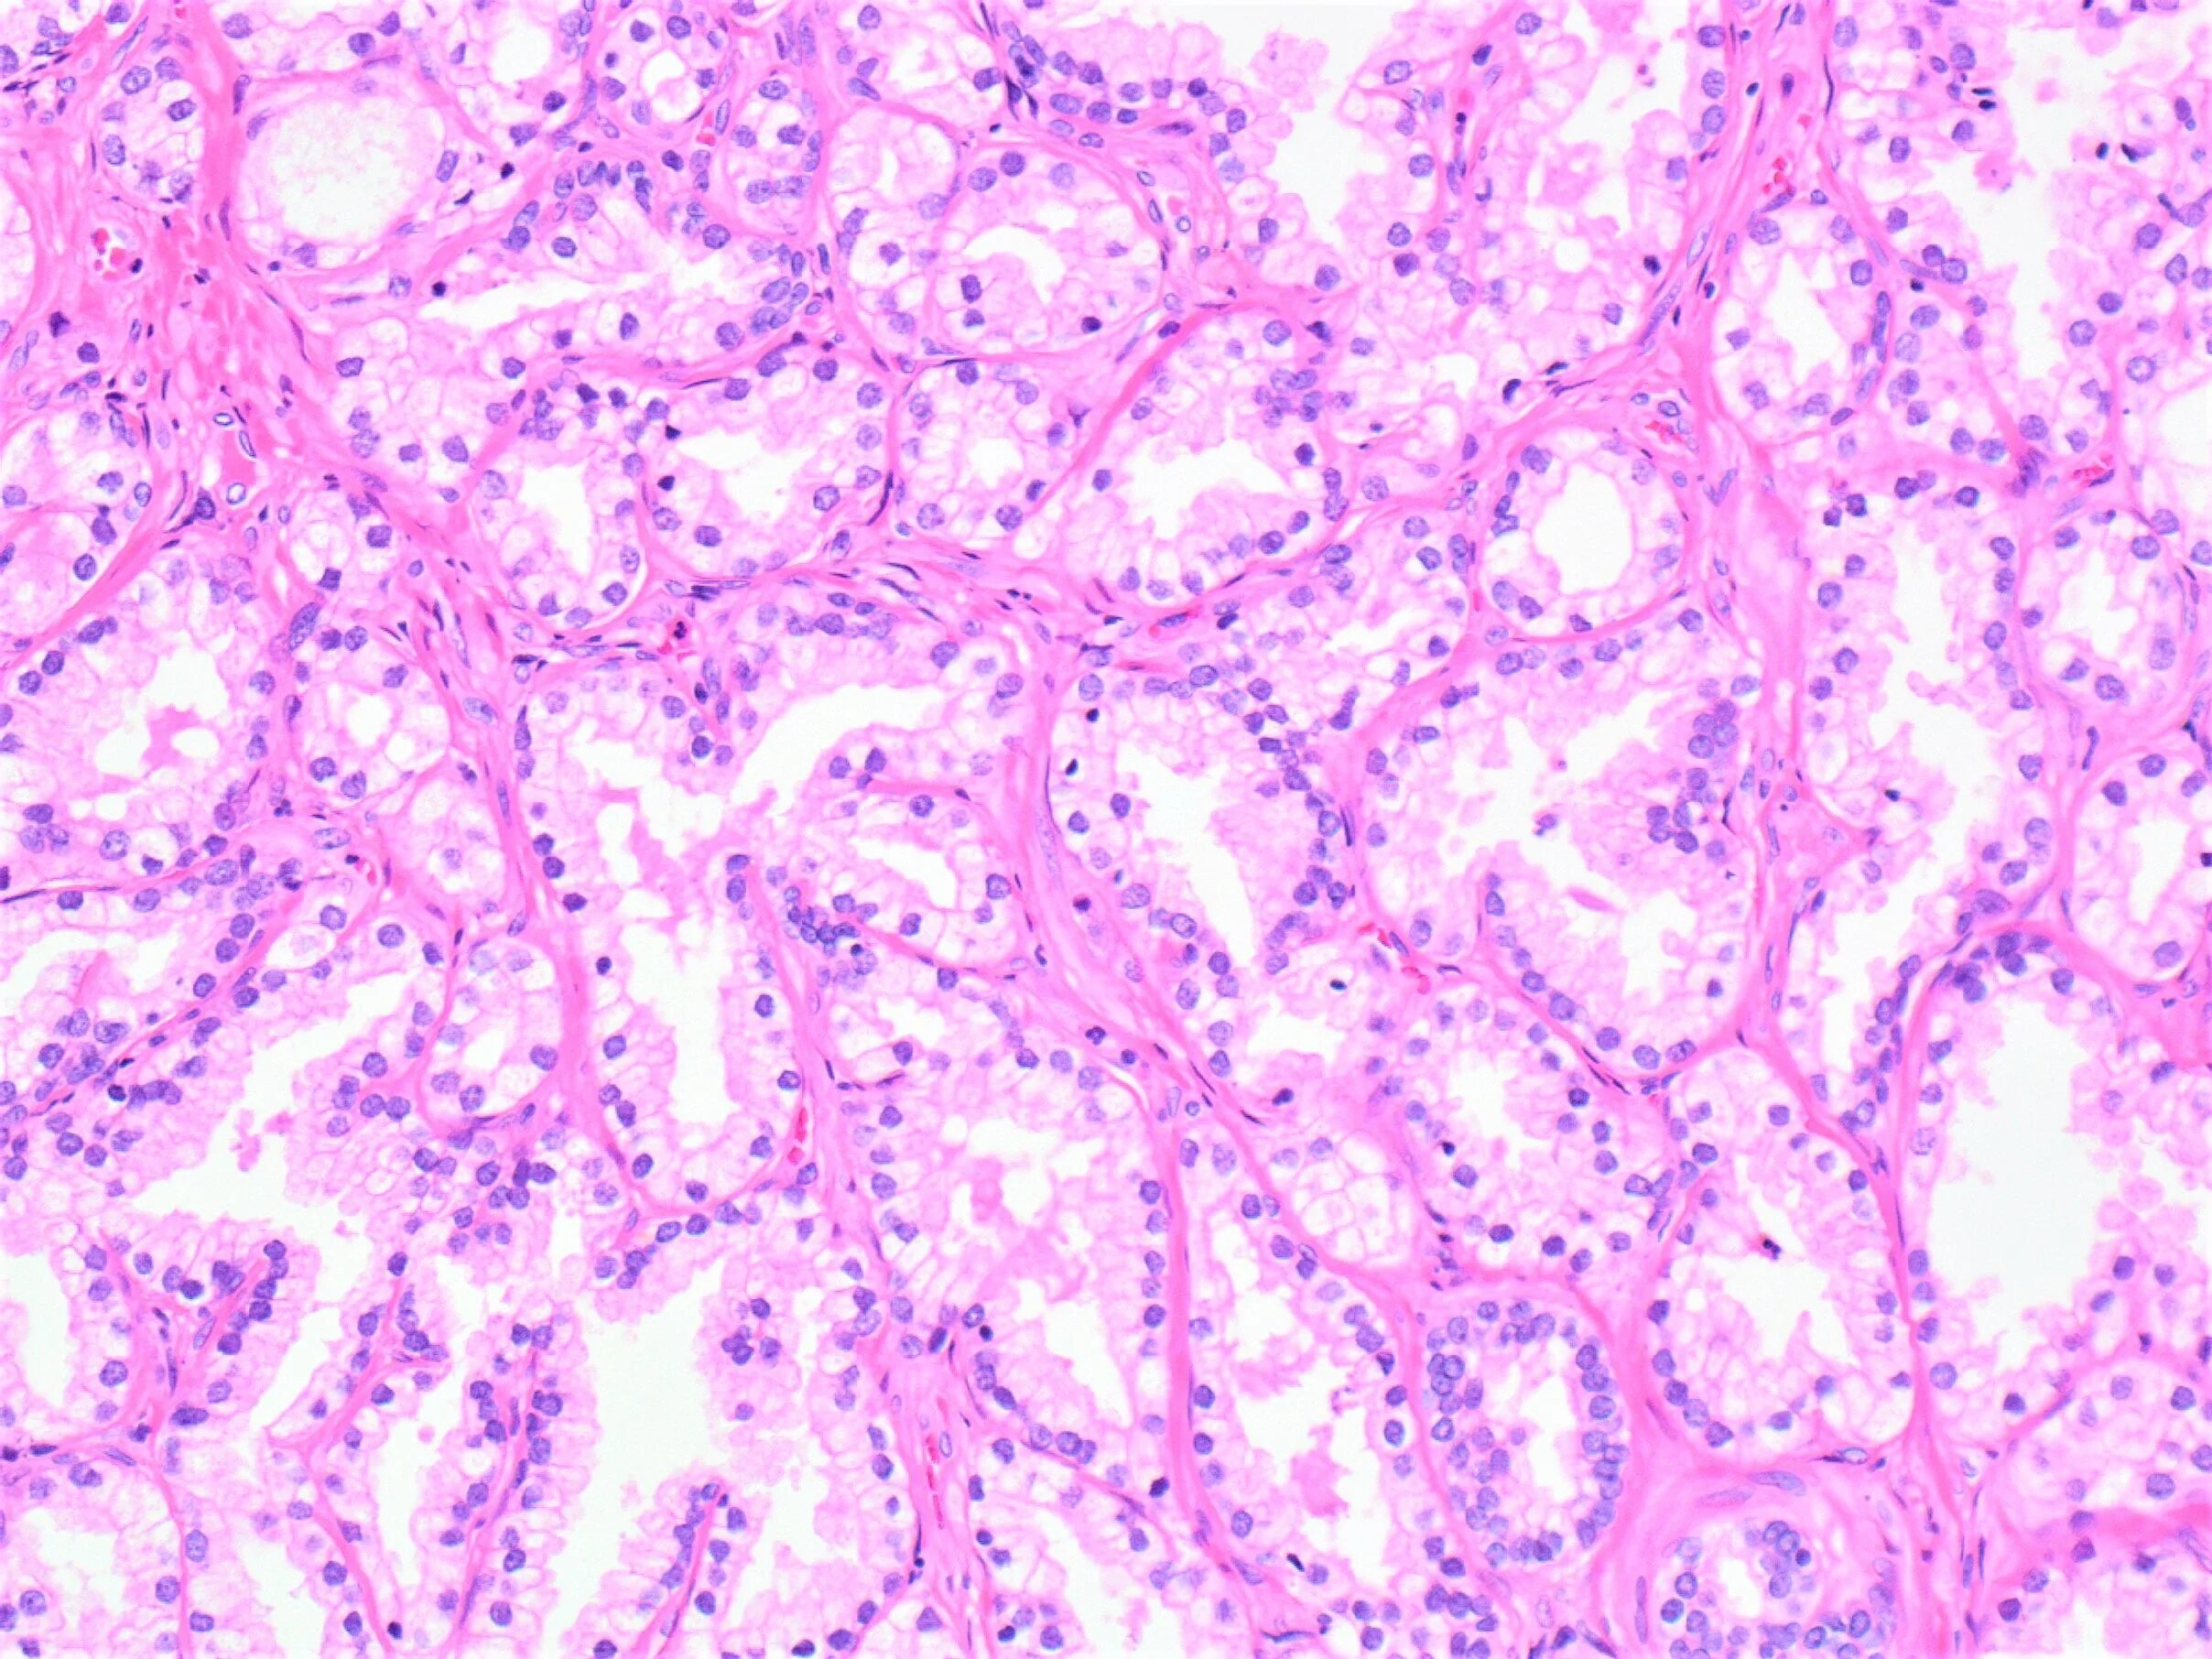

Подтверждена гистология